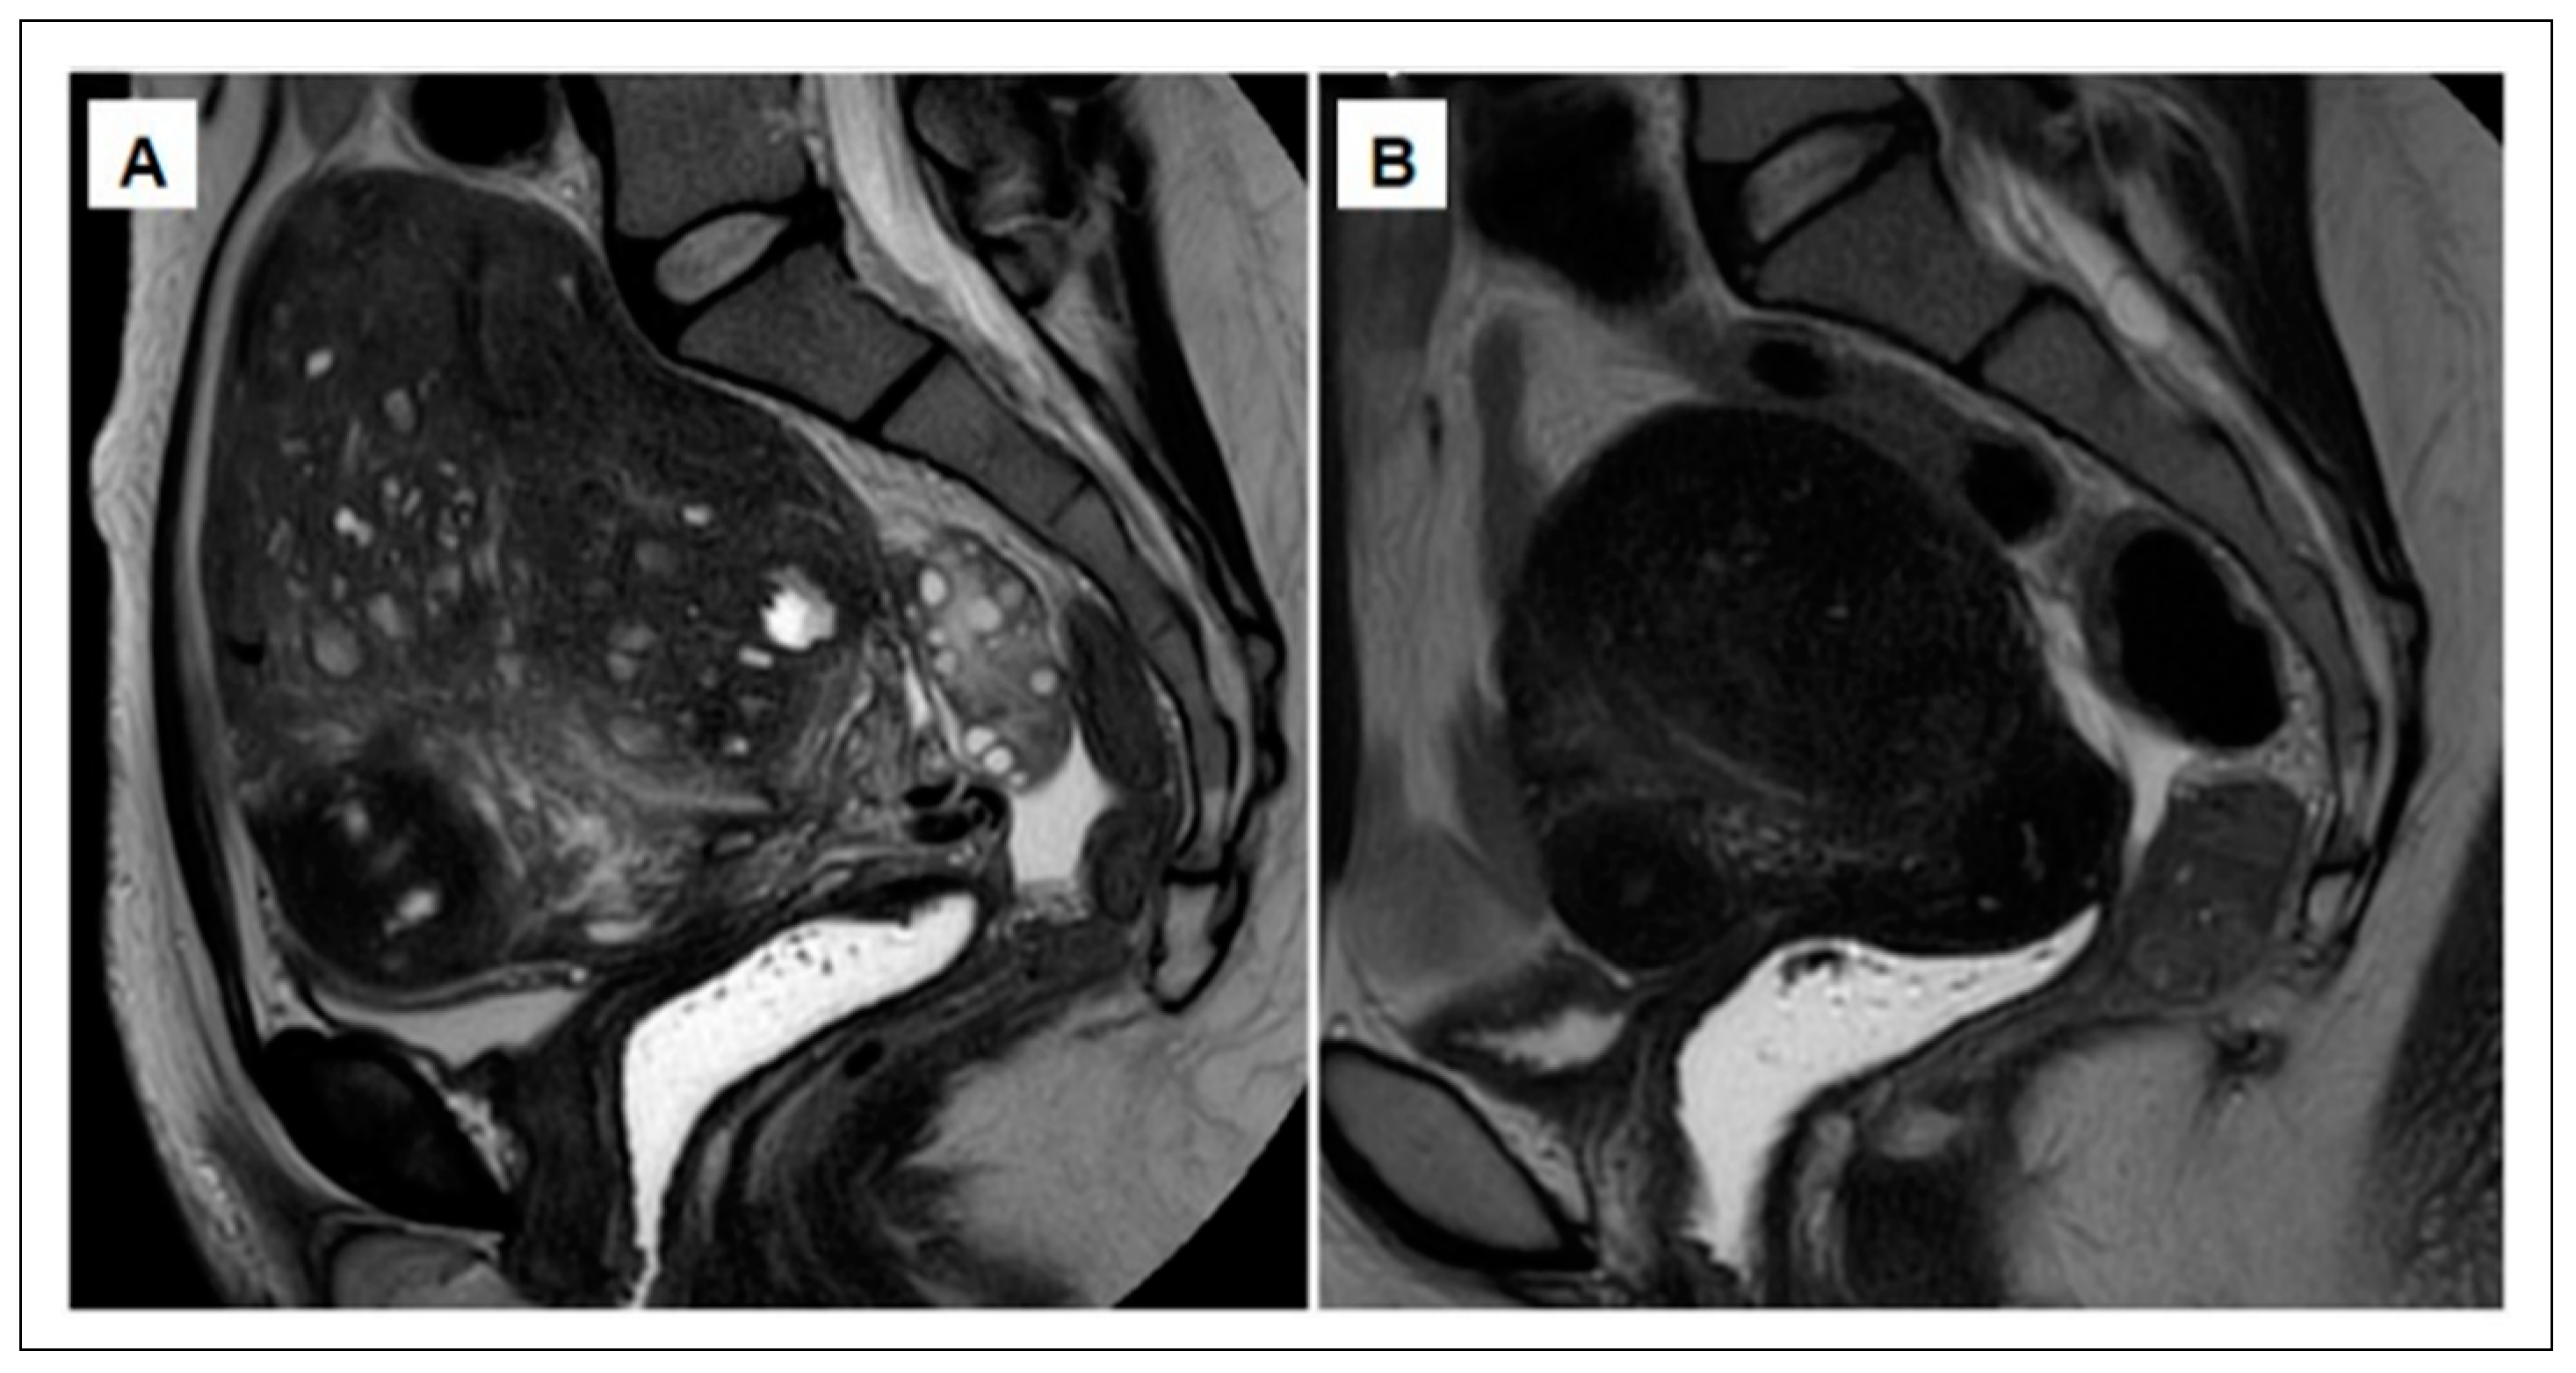

- Leyendecker, G.; Bilgicyildirim, A.; Inacker, M.; Stalf, T.; Huppert, P.; Mall, G.; Böttcher, B.; Wildt, L. Adenomyosis and endometriosis. Re-visiting their association and further insights into the mechanisms of auto-traumatisation. An MRI study. Arch. Gynecol. Obstet. 2015, 291, 917–932. [Google Scholar] [CrossRef] [PubMed]

- Chapron, C.; Tosti, C.; Marcellin, L.; Bourdon, M.; Lafay-Pillet, M.-C.; Millischer, A.-E.; Streuli, I.; Borghese, B.; Petraglia, F.; Santulli, P. Relationship between the magnetic resonance imaging appearance of adenomyosis and endometriosis phenotypes. Hum. Reprod. 2017, 32, 1393–1401. [Google Scholar] [CrossRef] [PubMed]